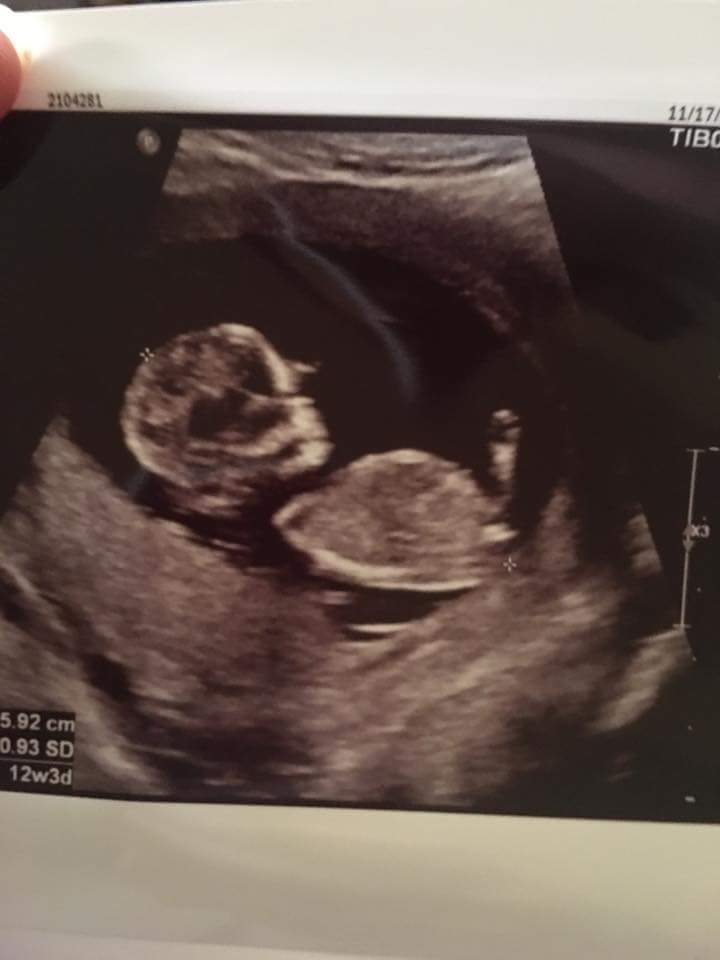

What does everyone think? Idk why but this nub is kinda tricky for me and that is exactly why i your help. This is for a friend so i appreciate all the help i can get!

maybe girl

Looks girly